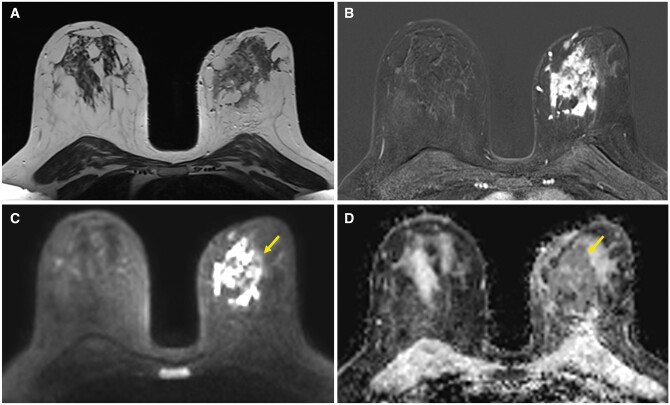

Idiopathic granulomatous mastitis (IGM) is an uncommon benign disease thought to have an autoimmune origin. After massive vaccination against COVID-19, mRNA vaccines have been associated with various possible adverse effects. Among those involving the breast, the most common are ipsilateral axillary lymphadenopathies and transient breast oedema. We present the case of a young woman who developed IGM after mRNA vaccination against COVID-19. We describe the clinical and imaging findings and management of this case, discussing the evidence for a possible link between vaccination and the development of this uncommon inflammatory process and underlining the importance of including this entity in the differential diagnosis in this scenario.